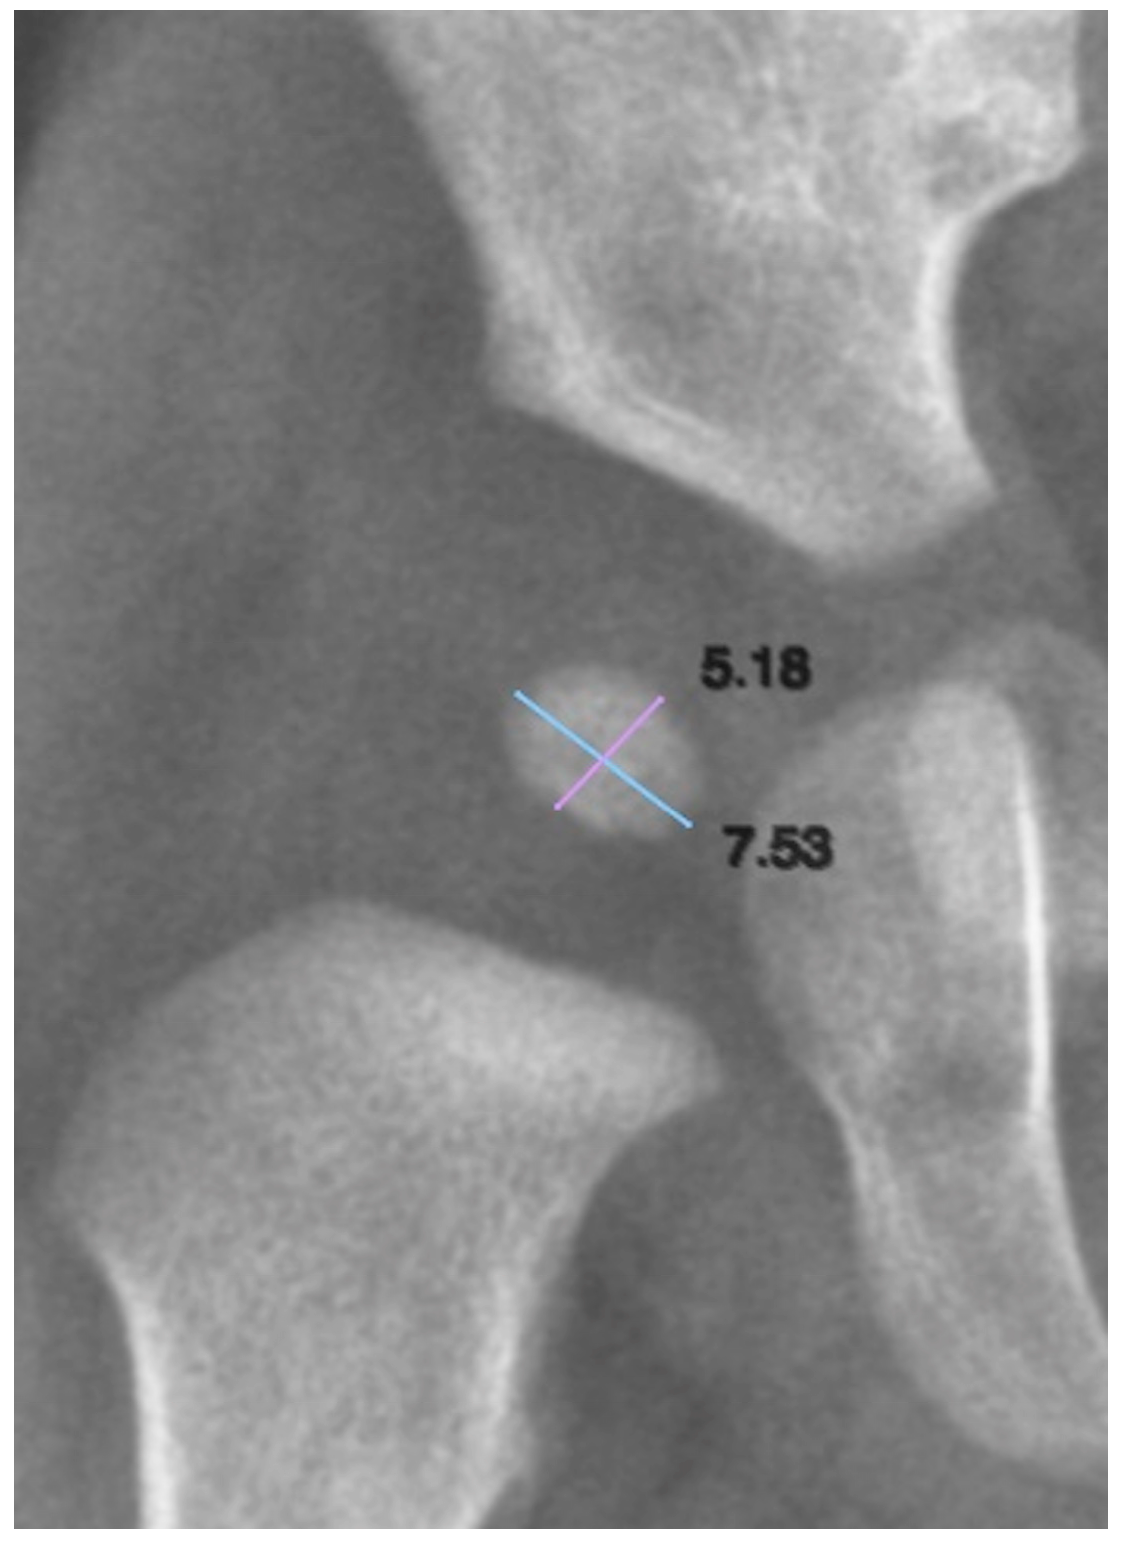

2.6. Biometry of the Ossification Nucleus

To quantify the size of the ONFH, both its longitudinal and transverse axes were measured. We defined the longitudinal axis as the superoinferior dimension and the transverse axis as the mediolateral dimension (Figure 2). These measurements allowed for the assessment of nucleus growth and symmetry in relation to age and other clinical variables.

Figure 2. Biometric assessment of the ossification nucleus of the femoral head. Light blue line: transverse measurement axis; Purple line: longitudinal measurement axis.